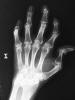

Carpo normal